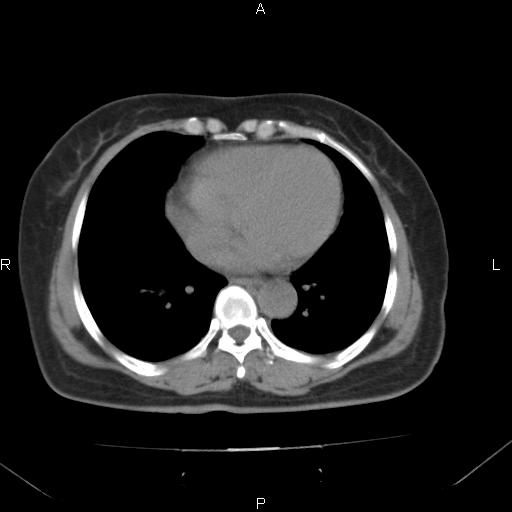

胸腺瘤

女、63Y 双眼睑下垂,早轻晚重。 胸腺瘤???

结果胸腺瘤